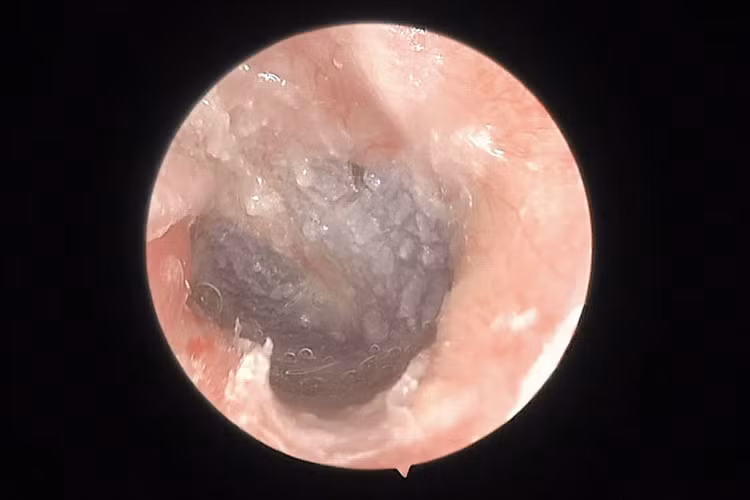

![]() |

| Sau 6 tháng phẫu thuật, bệnh nhân nghe tốt và không còn chít hẹp ống tai. Ảnh BVCC |